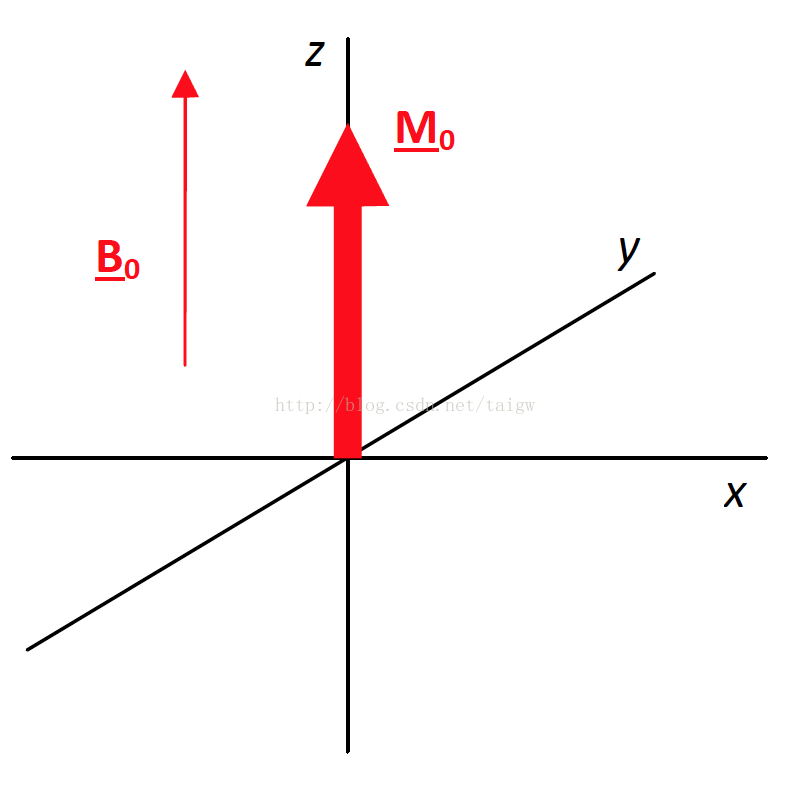

MRIは、磁気共鳴画像(Magnetic Resonance Imaging)の略称で、 強い磁石 と 電波 を使って体の断層像を撮る検査です。 MRIの原理は、まず強い磁気の中で、患者さんに外から電波を体に加えます。. ・骨盤部ではmriを,腹部ではctを第一選択にする. ・t1強調画像ではt1が長いほど磁化の回復が遅れるため信号が低く(黒く),t2強調画像ではt2 が長いほど磁化の減衰が遅れるため信号が高く(白く)描出される.t1とt2の組み合わせで組織 の成分が推定できる.. Mri造影剤は、mriにおける体内構造の可視性を向上するために使われる造影剤 。 コントラストの強調にはガドリニウムという化合物が最も一般的に使われる。 このmri造影剤は経口投与もしくは静脈投与(angio)により体組織内の核の緩和時間を短縮する。.

Nuclear Magnetic Resonance (Image). リウマチは関節内に存在する滑膜という組織が異常増殖し、関節内に慢性の炎症を生じる病気で、進行するとさまざまな機能障害を引き起こします 現在、当クリニックでは上腹部MRI検査として、横断像を4シーケンス<T1(in、 out Phase)T2 HeavyT2 DWI>、冠状断. T1強調像(Axial) T2強調像(Axial) 内膜症性嚢胞(チョコレート嚢胞) multiplicity.

高感度、人体に多く存在(水、中性脂肪) 横緩和時間が長い(信号をひろいやすい) T1強調画像、T2強調画像、プロトン密度画像.

磁共振中的t1 T2 和t2 的原理和区别 飞跃重洋的思念的博客 Csdn博客

核磁共振成像 知乎